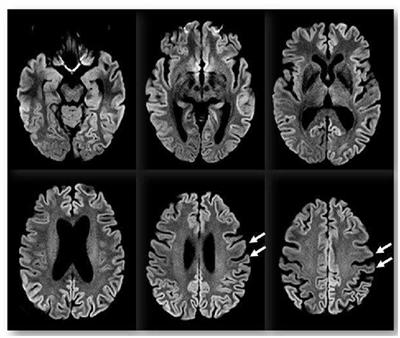

A doença é capaz de provocar desordem cerebral com perda de memória e tremores. Além disso, possui rápida evolução, e de forma inevitável, leva à morte do paciente.

Segundo a OMS, para definição de um caso suspeito da doença se baseia nas análises dos exames, sinais e sintomas e história epidemiológica do paciente. Desta forma, o caso pode ser definido como possível, provável e definitivo, mas a confirmação final só pode ser feita por meio da necropsia com a análise neuropatológica de fragmentos do cérebro. Porém, ainda não existe nenhum tratamento eficaz, no entanto o objetivo é aliviar a dor e os sintomas.